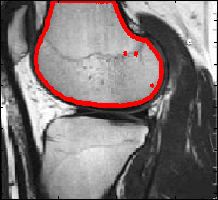

Using the previous objective function, it is now possible to segment the vessel image as shown below.

|

This picture shows that region based segmentation are not prune to leakage. However, the boundary may not be exactly where one think it would be. A mixture of edge based terms and region based terms in the objective function might be a good combination.